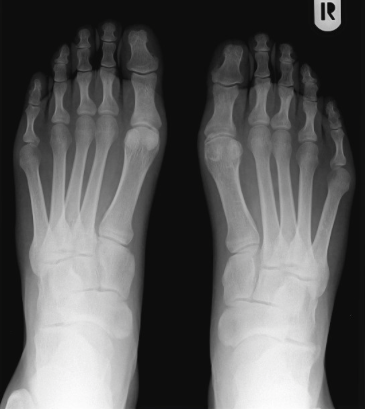

- 거골하관절을 외반시키는 근육

1. 종비인대파열시 대신할 수 있는 안정성을 만드는 근육

4. 장비골근은 횡아치를 만드는 중요한 근육

5. 장단비골근은 발의 족저굴곡, 외반근육